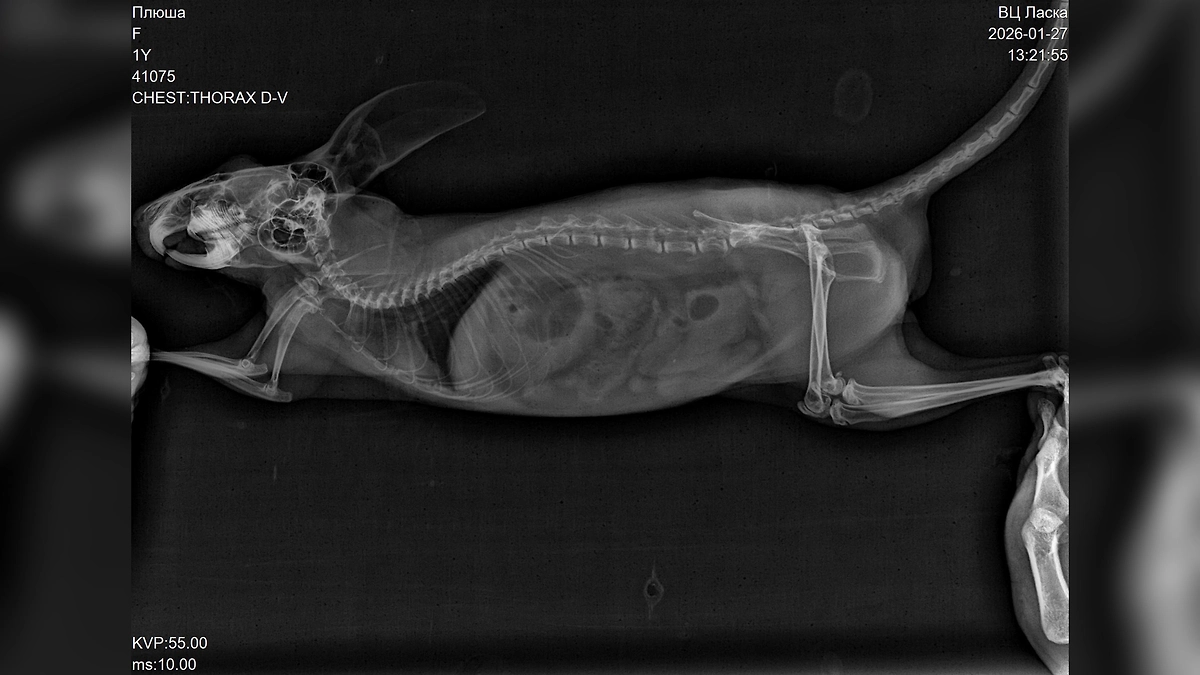

«За неё боролись около четырёх часов, но к сожалению, травмы оказались несовместимыми с жизнью. Диагноз — черепно-мозговая травма и отёк головного мозга», — написал он.

По словам Билана, он сначала предположил, что шиншилла могла получить травмы из-за кота Шахтёр, поскольку он хищник. Однако, по всей видимости, Плюша самостоятельно выбралась из клетки и с разбега врезалась в панорамное окно, что принесло тяжёлые травмы. Артист обратил внимание на то, как важно заранее понимать, с какими трудностями можно столкнуться, когда заводишь подобное животное.